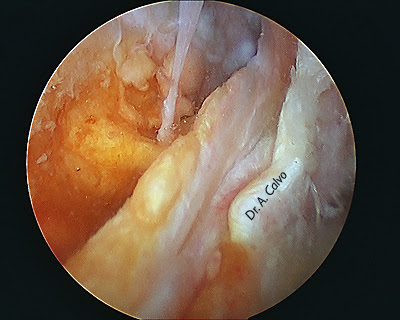

Desde una visión posterior Glenohumeral se marca el biceps con una sutura o una aguja (yo prefiero una aguja ya que el hilo con frecuencia se rasga) y se realiza la tenotomía.

Pasamos entonces a la visión SUBACROMIAL, realizamos una acromioplastia conservadora y localizamos la aguja que marca la PLB. En ocasiones localizar la PLB en el espacio subacromial puede ser lo más arduo y difícil, sobretodo si tenemos en cuenta que hay que evitar lesionar el manguito rotador.

Una vez localizada la aguja se libera la PLB abriendo con cuidado el intervalo rotador.

Debemos abrir la corredera bicipital para permitir la salida del biceps por el portal anterior. En el extremo del muñón de la PLB que hemos exteriorizado damos un punto de tracción con una sutura de alta resistencia.